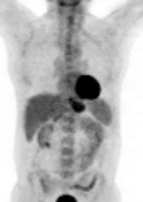

TEP-FDG : persistance d’un discret hypermétabolisme en regard de l’adénomégalie

axillaire droite isolée SUV max 2.0 , SUV max du bruit de fond avoisinant à 0.9.

Absence d’hypermétabolisme suspect au niveau des autres aires ganglionnaires.

Réponse métabolique partielle axillaire droite et réponse métabolique complète

sur les autres territoires.